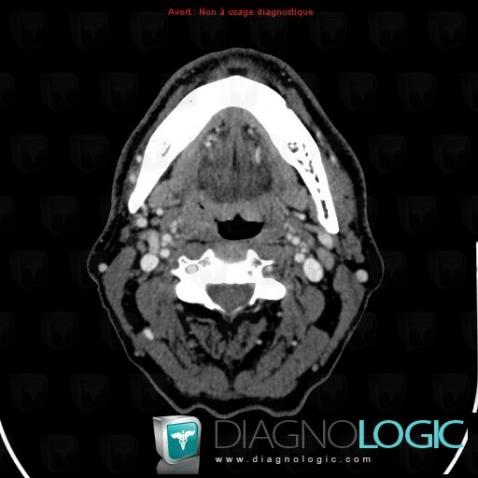

Tonsil cancer, Oropharynx / Floor-mouth, CT

Here is the specific information in the key image above:

- Diagnosis Tonsil cancer (link to Orophagyngeal neoplasm), Location(s) Oropharynx / Floor of mouth, with gamuts Oropharynx or floor of mouth non cystic mass